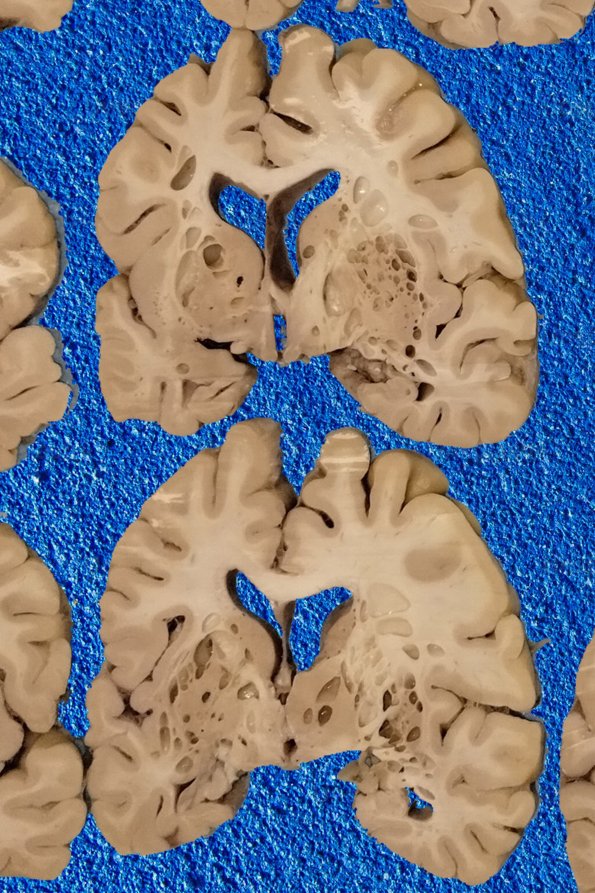

Selected sections of the gross specimen are shown at higher magnification in coronal section. There are numerous smooth walled lozenge-shaped cystic lesions which reflect the postmortem accumulation of the product of gas forming organisms.